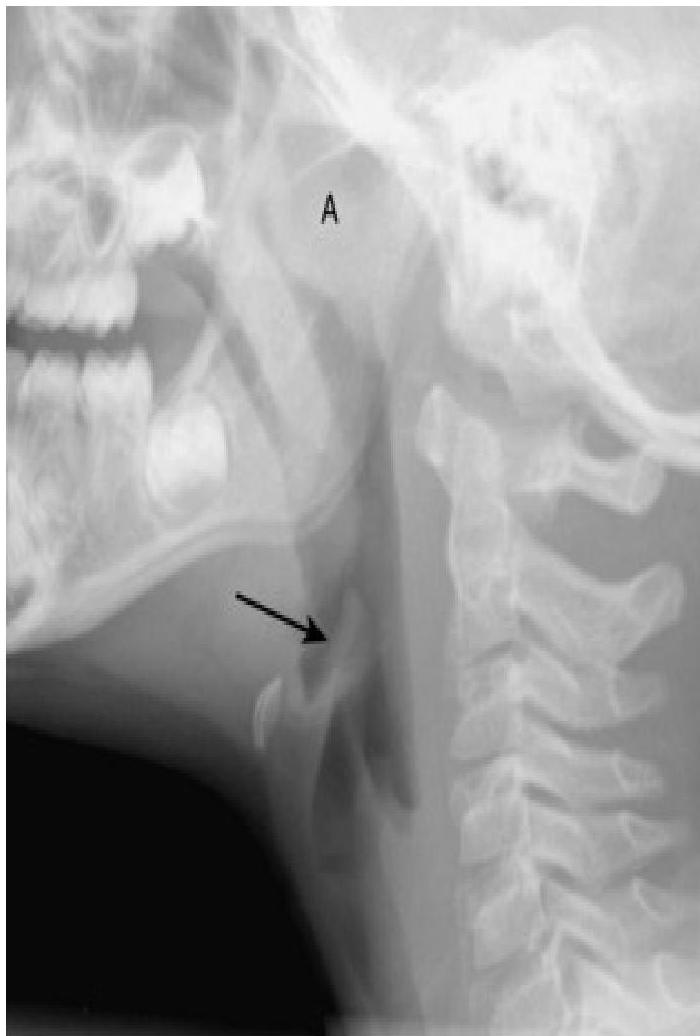

- Soft-tissue Lateral Neck Radiographs:

- Portable if possible.

- Positive in 80% of cases.

- Feature: An enlarged epiglottis protruding from the anterior wall of the hypopharynx (the “thumb sign”).

- Other findings: Thickened aryepiglottic folds, loss of vallecular air space, distended hypopharynx.